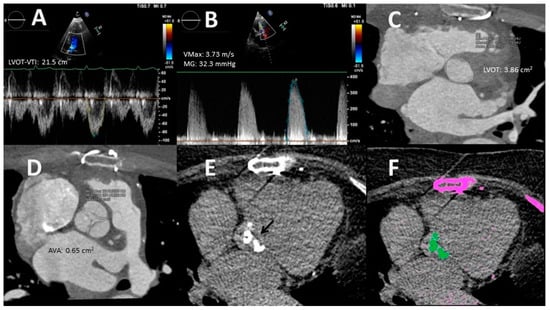

- Planimetry. MDCT allows 3D acquisition throughout the entire cardiac cycle using retrospective protocols. Through multislice reconstructions, planimetry of the AV orifice is feasible. Such a measure has shown good agreement with AVA estimated through the CEq [40]. Concerning LVOT size, MDCT assessment is considered to be the gold standard test [23]. Clavel et al. [41] observed that AVA calculated with a hybrid TTE–MDCT method in which the LVOT area used in the Ceq was obtained with MDCT predicted long-term survival with an optimal cut-off value of 1.2 cm2 instead of 1 cm2 [41].

- Pre-interventional study. Coverage of MDCT at acquisition can be extended to the ascending aorta to measure its diameter and determine the presence of calcifications. This information is helpful in cases where surgical valve replacement is considered. Regarding transcatheter aortic valve replacement (TAVR), CT is the reference technique for procedural planning. MDCT allows a precise estimation of the valve annulus size, its distance to the coronary ostia, and the caliber of the peripheral arterial vascular accesses. All of these parameters are essential to determine the candidacy for TAVR and to select the type and size of the prosthesis. Moreover, the incorporation of coronary assessment into CT protocols does not require an increase in contrast or radiation doses and has been shown to reduce the need for invasive coronary angiography in a noteworthy percentage of cases [42]. The use of the novel CT-derived fractional flow reserve technique is still not recommended because it may increase the number of false positive tests [43].